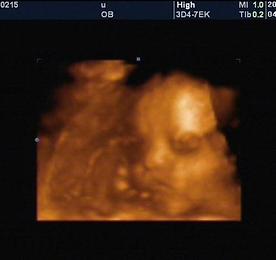

육아일기 썸네일형 리스트형 제주 중문의 주상절리대입니다. 사실 이런 해안은 이제 질립니다. 워낙 제주도에서 멋진 것들을 많이 봐와서... ㅎㅎㅎ 그래도 멋져보이죠? 더보기 점심에 먹은 제주 제육볶음입니다. 돼지고기에 콩나물과 파를 넣고 볶아서 먹는 것입니다. 식당 이름은 생각이 잘 안나는데... 쩝... 제주에서 정말 유명한 집인데... 정말 맛있습니다~ *^^* 더보기 28주 5일에 찍은 태양이 입체 초음파 사진입니다. 2009년 6월 12일에 찍은 태양이 입체 초음파 사진입니다. 28주 5일되는 날이었는데 이제야 올립니다. 제주도 사진도 아직 다 못올렸는데... ㅋㅋ 아무튼 요즘 정신 없는 나날을 보내고 있습니다. 6월 30일까지 논문을 완료해야 해서 거의 매일 새벽 1~2시 까지 연구(?)를 하고 있습니다. 이제 조금 정리가 되어 가는 느낌입니다. 우리 태양이 사진좀 보세요! 눈도 크고 코도 오똑 하네요~^^ 와이프 말이 자기 닮았다고 하던데.. 다행입니다. 진짜 저 닮으면 안되는데~ ㅎㅎㅎ 동영상도 있는데 지금은 사정상 올리지 못하고... 다음 기회에 올리도록 하겠습니다. 우리 이쁜 태양이 공주님 함 보세요! 더보기 제주 천지연폭포입니다. 제주도를 대표하는 천지연폭포입니다. 제주의 폭포하면 천지연이 생각날 정도로 유명한 폭포이지요... 물이 많치 않아서 화려해보이지는 않지만 그래도 그 장엄함에 감동하게 됩니다. 그리고 폭포를 보면서 폭포소리를 듣고 있자니 스트레스가 풀리는 기분이었습니다. 더보기 제주 올레길입니다. 울창한 숲.. 정말 좋습니다! 제주 한화콘도에서 하룻밤을 자고 천지연폭포로 이동하였습니다. 제주시에서 서귀포시로 넘어가는 것입니다. 제주도를 관통한다고 해야 하나? 제주도를 관통하다가 정말 울창한 숲을 발견하였습니다. 하늘 높이 솟은 나무들이 인상적이었습니다. 잠시 내려서 맑은 공기와 함께 산책을 했습니다. 이런게 바로 제주 올레길이라고 하더군요... ^^ 정말 이런게 가장 좋은 것 같습니다!!! 더보기 한라산 깊숙히 자리잡은 한화콘도! 제주도의 첫날밤! 숙소는 한화콘도로 정했습니다. 제주 한화콘도는 정말 깊은 산속에 있더군요~ 그런데 이 깊숙한 한라산 내에 콘도와 함께 엄청난 골프장이 들어서 있더군요~ 돈 있는 사람들은 이곳에 숙박하면서 골프를 즐기는구나... 하는 생각을 하니 좀 씁쓸한 생각도 들었답니다. ㅎㅎㅎ 한화콘도 주변의 그림같은 풍경입니다. 정말 멋진 곳입니다. 더보기 저녁은 제주 유리네식당에서 갈치조림과 성게알미역국으로... '유리네식당'이 유명하다고 하여 찾아갔습니다. 처음에는 이름이 시원찮아서(?) 반신반의했는데 막상 들어가 유리네식당을 다녀간 수많은 유명인들의 싸인을 보니 그 유명세를 실감하게 되었습니다. 갈치조림과 성게알미역국이 유명하다고 하여 주문했습니다. 갈치는 정말 부드럽더군요~ 휴~~~ ^^ 거기다가 성게알미역국도 색다른 맛이었습니다. 제주에 들르실 기회가 된다면 한번 들러보시기 바랍니다. 제주 맛기행은 앞으로 계속됩니다~ ^^ 더보기 제주 협재해수욕장에서 화보를 촬영했습니다. 한림공원에서 나와 바로 옆에 있는 협재해수욕장에 들렀습니다. 제주도에서도 유명한 해수욕장이라고 합니다. 이곳에서 화보를 촬영했습니다. ㅎㅎㅎ 그냥 아무곳에나 서서 찍어도 화보가 됩니다. 마지막사진이 좀 깬다~ ㅎㅎㅎ 더보기 제주 한림공원 2편! 사진이 엄청 많네요~ ㅎㅎㅎ 제주 한림공원에서 한거라고는 이렇게 사진 찍은거 밖에 없는 것 같습니다. 엄청 힘들었던 기억이 납니다. 한 두시간정도 돌아다녔나? 한림공원내에 동굴도 있더군요~ 정말 넓은 공원이었습니다. 멋있기도 하구요~ ^^ 더보기 제주 한림공원 1편! 제주도에는 이런 공원이 엄청나게 많더군요~ ^^ 삼성혈에서 맛있는 점심을 먹고 한림공원을 찾아갔습니다. 제주도! 정말 공기 맑고 물 좋은 곳이더군요~ ^^ 제주도 공원에 서식하고 있는 열대식물들입니다!! 더보기 이전 1 ··· 12 13 14 15 16 17 다음